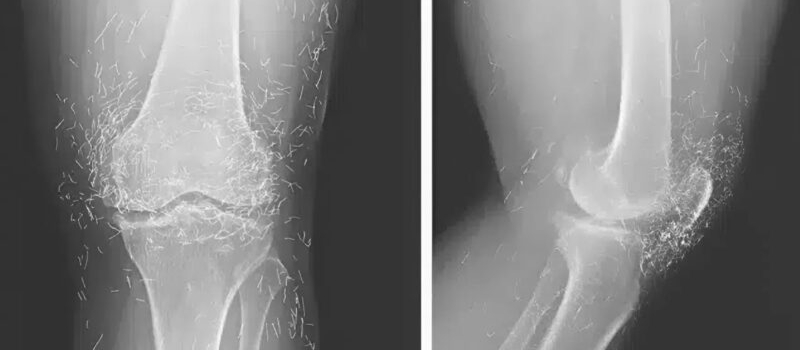

When the images arrived, everything changed. The nurse who brought them in froze by the door. “Doctor… you need to see this.” I took the envelope, pulled out the film, and held it against the light. For a second, I couldn’t comprehend what I was looking at. Her knee joint shimmered with dozens of tiny, metallic streaks — arranged in perfect symmetry.

At first, I thought it was an error — maybe a reflection, a machine glitch. We repeated the scan. The same strange pattern appeared again. I adjusted the magnification, leaned closer to the screen… and then felt a chill run down my spine. Those streaks weren’t reflections. They were real. They were inside her. 😱

When she finally came to us, the inflammation was advanced. The X-rays showed what her faith had hidden: over thirty golden needles embedded in soft tissue, surrounded by infection and scar. The body had fought them all these years — forming capsules of fibrous tissue around each invader, as if building tiny prisons inside her flesh. But some capsules had ruptured, releasing toxins.

We scheduled emergency surgery. Under anesthesia, I studied her knee one last time on the monitor. The needles sparkled like constellations — Orion, Cassiopeia, stars trapped beneath her skin. 🌌 The image was hauntingly beautiful and unbearably tragic.